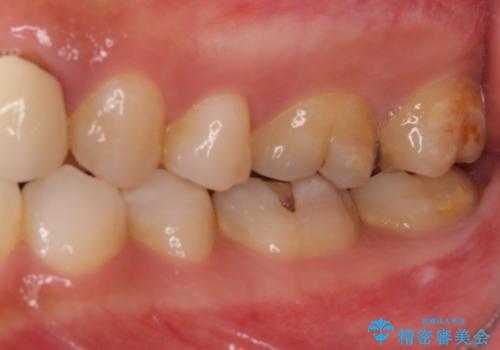

- 審美的ではない上の前歯とデコボコの下の前歯、歯茎が腫れている奥歯を気にして来院された患者様です。

根管治療の必要な歯がいくつかあるため、まずは根管治療を行い、その後インビザラインにて矯正治療を行うこととしました。

矯正治療後に前歯をセラミックブリッジに、奥の銀歯はセラミックインレーやPGAインレー(ゴールドインレー)にて補綴・修復治療を行うこととしました。